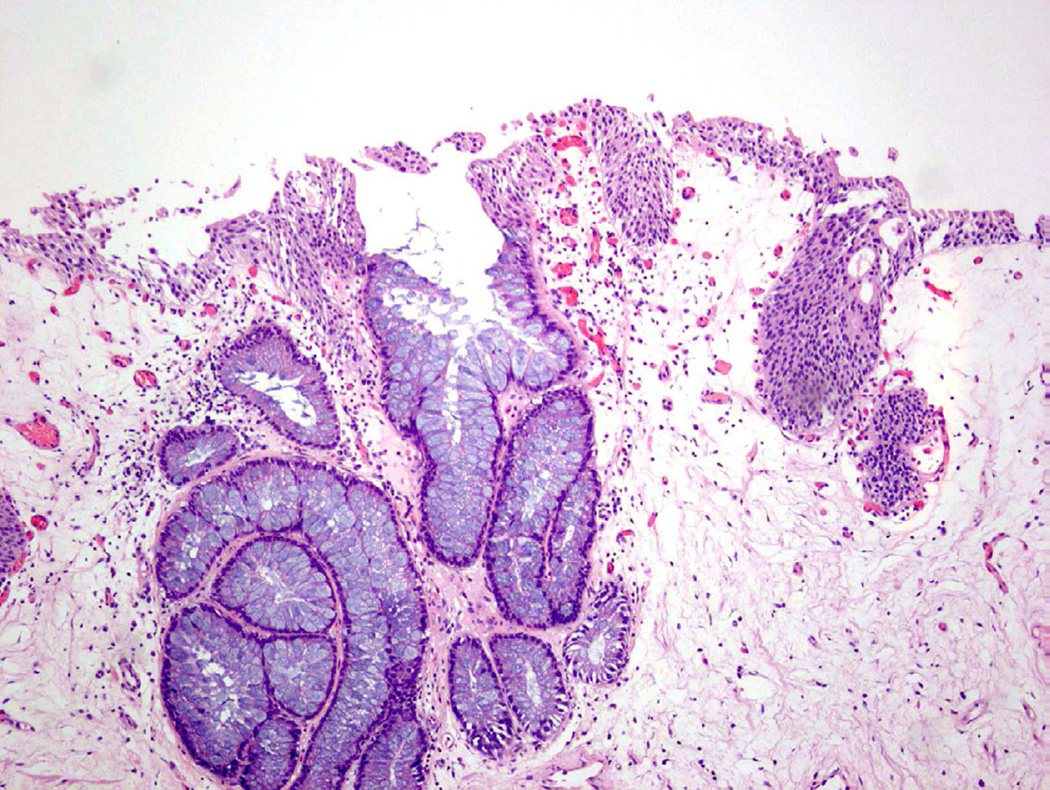

Cystitis cystica et glandularis

Cystitis cystica et glandularis (CCEG) is a benign process defined as cystic changes within von Brunn nests (cystitis cystica) that develop metaplastic changes of the cellular lining to columnar or cuboidal epithelium (Fig. 11)23. Similar to other metaplastic processes, CCEG is attributed to chronic inflammation/irritation and favors, but is not restricted to, the trigone of the bladder. CCEG is further subdivided into usual and intestinal types, although in practice this sub-categorization is often not frequently used.

Figure 11.

Cystitis cystica et glandularis.

Intestinal metaplasia

Intestinal metaplasia (IM) is a proliferation of epithelium in the urinary bladder characterized by gland-like structures lined with mucin-secreting cells (Fig. 12)24. These mucin-secreting cells resemble goblet cells, which are found in the colonic mucosa of the lower gastrointestinal tract23. In a study by Corica et al., 53 cases of IM in the bladder were evaluated with long-term follow up (mean >12 years among the two case groups24). The authors determined that the presence of IM was not a strong risk factor for the development of overt malignancy24. Smith et al. evaluated 19 cases of IM and found no evidence carcinoma at follow-up (mean 4.4 years23). Additionally, while 37% of the cases with IM had co-existing carcinoma, the authors felt that the association between the two processes did not imply that IM was the precursor lesion23. One study has suggested that pure adenocarcinomas of the urinary bladder (as opposed to urothelial carcinoma with glandular differentiation) are derived from IM, but attempts to definitively associate IM as pre-malignant has yet to be proven25. Extensive IM has been suggested to predispose patients to a greater risk for developing adenocarcinoma, but this frequently cited association is based on a single study26 and no additional evidence has been identified in the current literature.

Figure 12.

Intestinal metaplasia showing mucin-containing goblet cells.